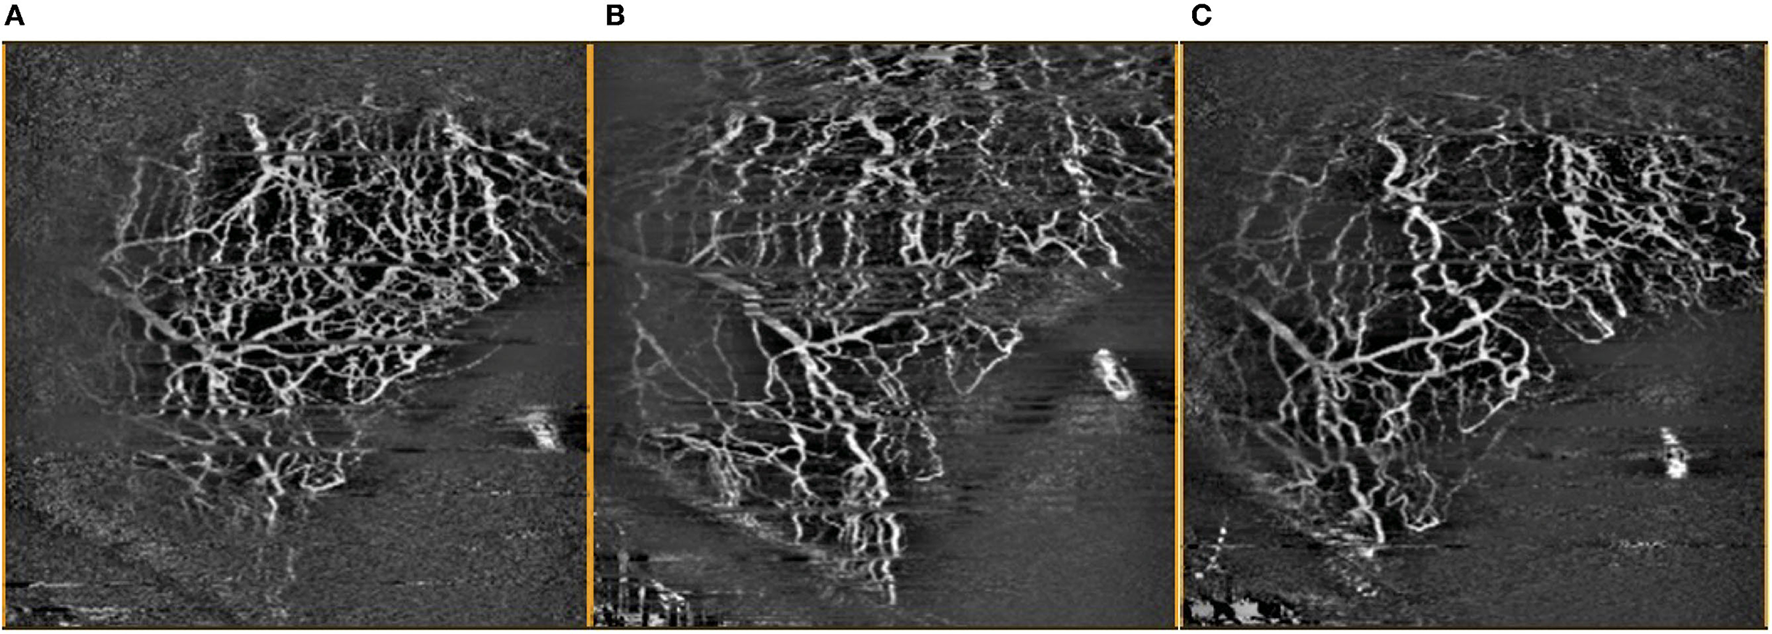

Vessel densities obtained from control sectors without implants were compared to vessel densities from sectors with the Hydrus Microstent in the same eye, with serial comparison analysis performed over the follow-up period (Figure 4). Statistical analysis was performed using Statistical Program for Social Sciences version 27.0.1.0 for MacOS© (2020 SPSS© Inc. IBM Corp, USA). Percentage differences in vessel densities were evaluated using Friedman Test (serial measurements over follow-up) and Wilcoxon Signed Rank Test (paired, compared to baseline). All data were expressed as mean ± standard deviation (SD) when applicable, and P < 0.05 were considered statistically significant.

Figure 4. Comparison of OCTA images of inferior temporal episcleral vessels taken (A) pre-operatively, (B) 1 month post-operatively, and (C) 3 months post-operatively, with artefacts removed.